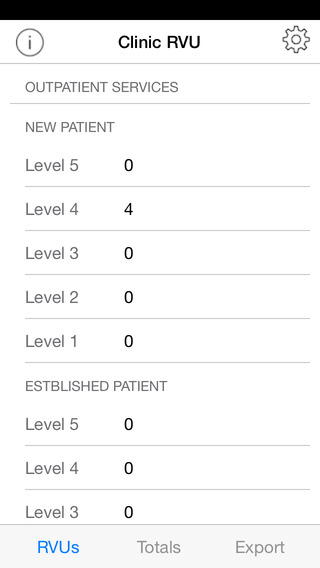

| 熱門國家 | 系統支援 | 版本 | 費用 | APP評分 | 上架日期 | 更新日期 |

|---|---|---|---|---|---|---|

| 未知 | Android Google Play | 1.50001 App下載 | 免費 | 1970-01-01 | 2015-04-24 | |

| 台灣 Taiwan | Android Google Play | 1.50001 App下載 | 免費 | 2014-06-02 | 2015-01-14 |